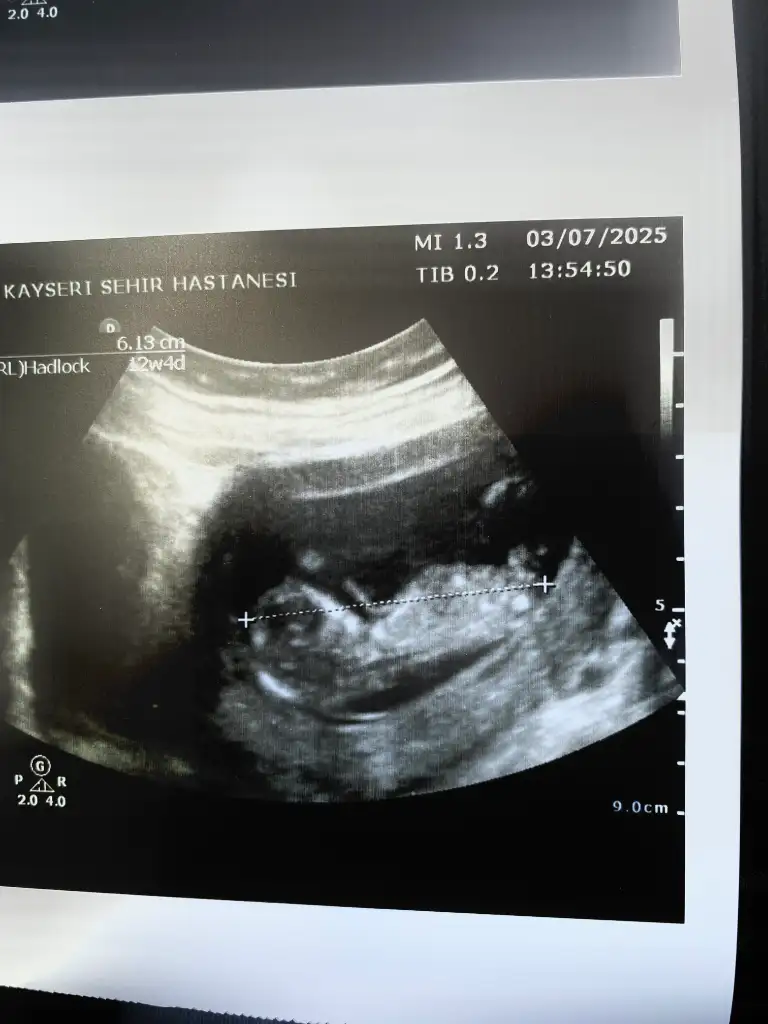

Kızlar 14 haftalık yeni ultrason doktor yine bilgi vermedi cinsiyet için varmı tahmini olan

bunlarda benim torunlarım 13 haftalık ,

doktor erkek demiş , ama yanılma olurmu anlayan var mı